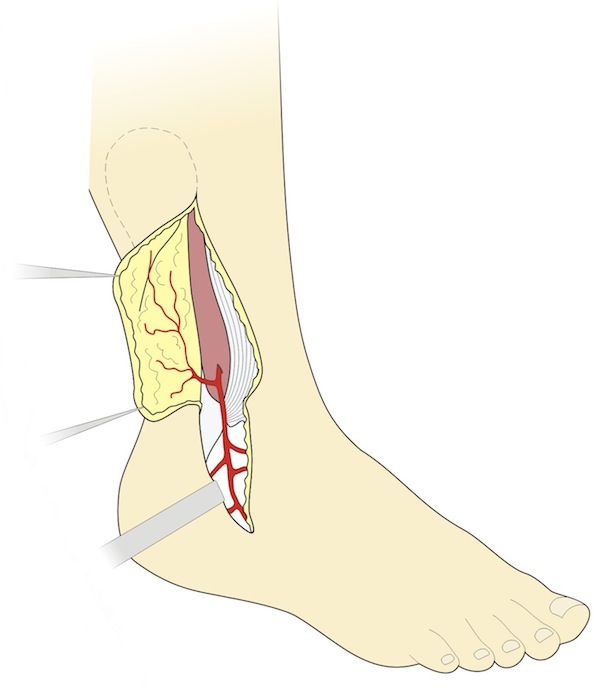

Островковый лоскут на проксимальном основании

Соответственно способу формирования сосудистой ножки возможно два типа кровоснабжения, однако кожная часть лоскута остается неизменной. Дистальный край лоскута должен доходить до уровня выхода перфорантной ветви малоберцовой артерии, которая может быть найдена путем пальпации в борозде выше и кпереди от наружной лодыжки. Дессекция начинается с переднего доступа, и продолжается до обнаружения перфорантной ветви (рис. 4). Сам лоскут, при этой препаровке, включает кожу, подкожную ткань и фасцию, но поверхностный малоберцовый нерв должен быть сохранен, чтоб избежать нарушения чувствительности на тыле стопы. В некоторых случаях возможно включение ветви этого нерва в состав лоскута для обеспечения чувствительности лоскута, но эта процедура требует наложения шва на нерв в реципиентной зоне [5].

Рис. 4. Дессекция и поднятие лоскута, включающего апоневроз. Поднятие лоскута осуществляется c переднего разреза до обнаружения перфорантной артерии и обнажения её кожной ветви.